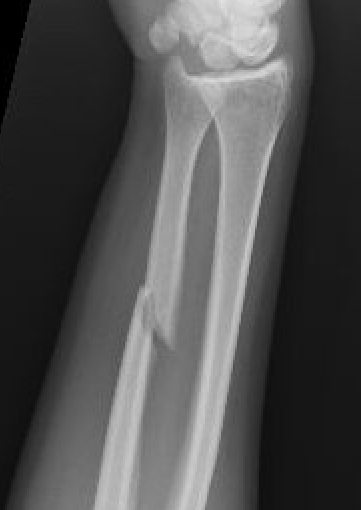

Location

Distal 1/3

Midshaft / middle 1/3

Proximal - beware Monteggia / radial head dislocation

Nonoperative management

Indications

Minimally displaced fractures

- < 50% displaced

- < 10 degrees angulation

Increased nonunion rates with midshaft versus distal fractures

- increased nonunion with midshaft (30%) versus distal 1/3 fractures (2%)